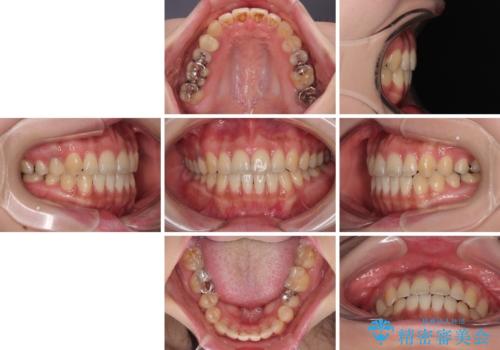

開咬をワイヤー装置で矯正治療

- 上下前歯が非接触となっている咬み合わせを気にして来院された患者様です。

治療開始から8ヶ月ほどで遠方への転勤が決まりましたが、歯列は概ね整っていたため、その後は東京出張を狙って治療を終える処置を行うことができました。